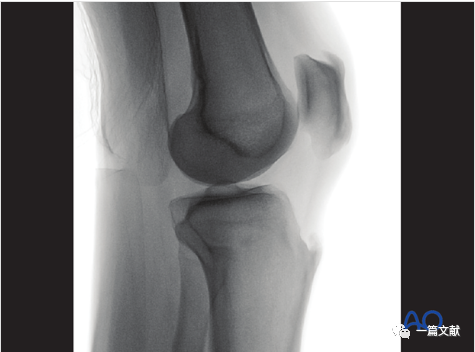

1)体位:在标准侧位基础上,将患肢外展10°-20°。如下图:

2)此标准位片的评估:1、稍突起的外侧平台关节面位于呈凹陷状的内侧关节面的头端;2、外侧胫骨平台面位于图像中央。如下图:

3)解剖标志的识别:如下图:凸起关节线为外侧胫骨平台。

4)此位片的意义:1、评估外侧平台关节面情况;2、检视是否有内固定穿透外侧平台。